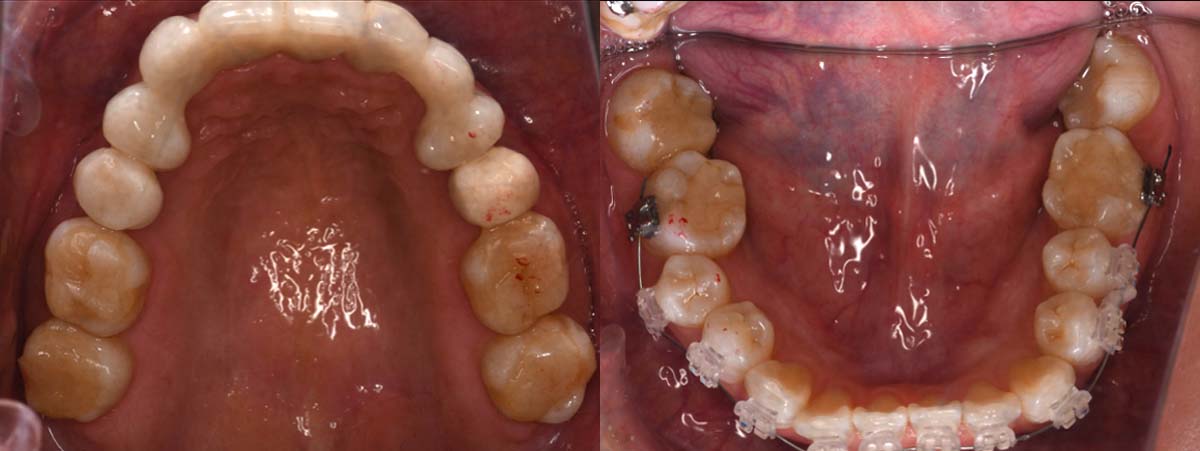

2024年 10月 下顎MTM開始

9月25日

姿勢の変化

2024年 3月 初診時

2024年 10月10日

2025年 12月25日